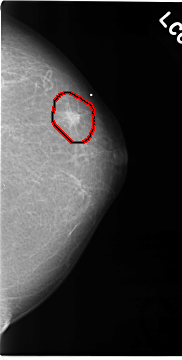

C_0118_1.LEFT_MLO

FILE: C_0118_1.LEFT_CC.OVERLAY

TOTAL_ABNORMALITIES 1

ABNORMALITY 1

LESION_TYPE MASS SHAPE IRREGULAR MARGINS SPICULATED

ASSESSMENT 5

SUBTLETY 5

PATHOLOGY MALIGNANT

TOTAL_OUTLINES 1

BOUNDARY